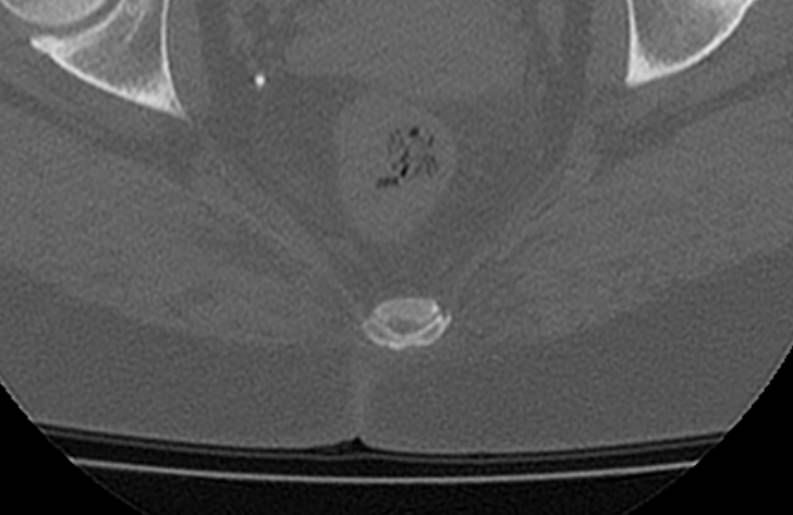

Для диагностики даже незначительных патологических изменений в различных отделах позвоночника, особенно в случае распространенного поражения, применяется один из современных наиболее информативных методов обследования – мультиспиральная компьютерная томография всего позвоночника. Методика основана на использовании проникающей способности рентгеновских лучей через органы и ткани человека и позволяет получить подробное изображение всех структур позвоночного столба. В комплексное обследование входит исследование шейного, грудного, пояснично-крестцового отделов позвоночника и копчика.

В медицинских центрах «Доступная медицина» сканирование всего позвоночника выполняется на новейших мультиспиральных компьютерных томографах последнего поколения TOSHIBA AQUILION в различных модификациях. Особенностью данных аппаратов является их способность проводить от 64 до 128 тончайших срезов одномоментно с минимальной толщиной от 0,5 мм.

Увеличенное количество высокочувствительных детекторов, которыми оснащены томографы, позволяет получать послойные снимки высокого качества с большой скоростью. Эта особенность данных аппаратов обеспечивает быстроту выполнения сканирования. При этом пациент получает минимальную дозу облучения, что имеет важное значение, особенно при такой обширной зоне исследования, как позвоночный столб.